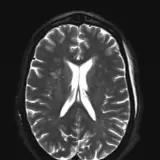

Over 2,100 interactive radiology cases, curated by radiologists for your level of training. Scroll, window, and view cases full screen — just like on PACS. Click linked findings in each writeup to jump straight to them on the image. Cases include sample reports, a focused discussion section, original illustrations, and videos.

Casos totalmente interativos com as ferramentas que você espera em um PACS — rolagem, ajuste de janela, zoom, movimentação, medidas, ROIs e modo de tela cheia.

Anotações detalhadas destacam os achados principais diretamente nos casos. Clique nos achados vinculados nas descrições dos casos para ir ao local exato no exame.

Role, movimente, ajuste janela e amplie como em uma estação PACS do trabalho